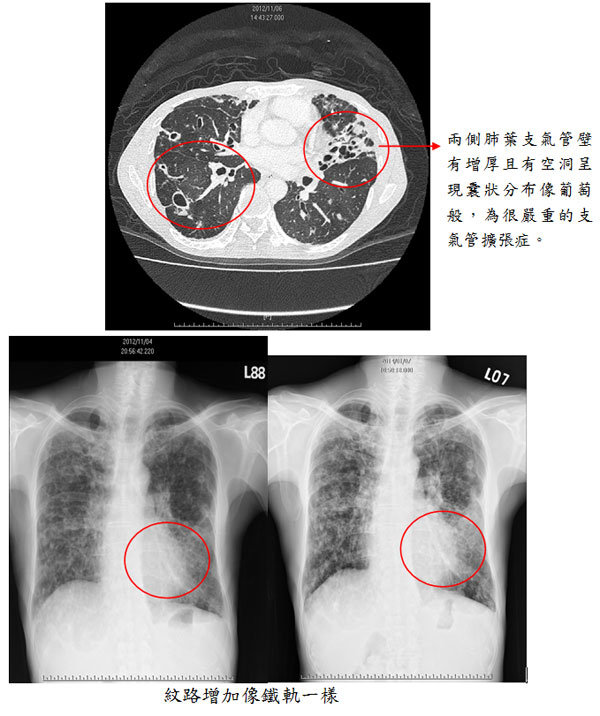

【案例一】 黃女士,75歲,不抽菸,主訴長期咳大量濃痰液,甚至會咳血。此病人因小時後肺炎感染沒有好好治療導致支氣管壁被破壞,來台以後經由電腦斷層檢查,兩側下肺葉支氣管壁有增厚且有空洞呈現囊狀分布像葡萄般,為很嚴重的支氣管擴張症。痰液檢查也多次分離出綠膿桿菌(學名:Pseudomonas aeruginosa)。病患因病情需要,必須長期服用氣管擴張劑與化痰藥合併姿勢引流背部扣擊,使痰液較易引流出,若痰液增加且顏色變黃或濃稠甚至咳血時,必須緊急就醫給於適當抗生素使用,避免嚴重肺炎減少病情惡化。

「支氣管擴張症」就是指支氣管壁黏膜破壞導致纖毛脫落清除痰液受損易感染,甚致破壞整個支氣管壁導致支氣管之微血管暴露易咳血且管壁纖維化,導致支氣管壁變厚且無彈性,所以在胸部X光可看見紋路增加像鐵軌一樣,甚至厲害的話像蜂窩一樣不正常的影像。因支氣管壁受損進而影響其排痰功能,所以易導致反覆性肺炎發生,並且常合併有咳血症狀。